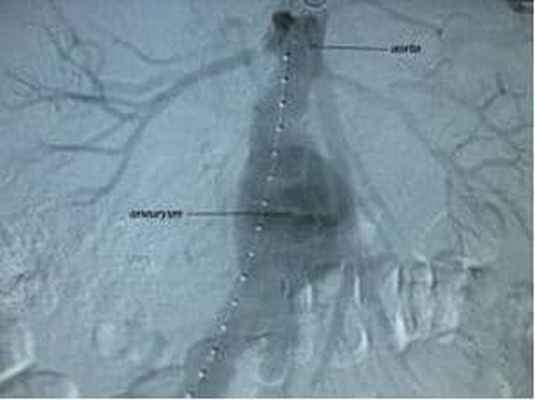

Более современный метод лечения аневризмы брюшной аорты, относящийся к гибридной хирургии. Данный метод сочетает в себе открытые хирургические технологии с эндоваскулярными, он представляет собой замену аневризматически расширенного участка аорты изнутри с использованием специального протеза, изготовленного в большинстве случаев «под заказ» (этим объясняется его высокая стоимость). Сосудистый протез специальным образом уложен в системе доставки. Его расправляют прямо в полости аневризмы, под контролем рентген-установки. Таким образом, протез исключает воздействие системного артериального кровотока на слабые растянутые стенки аорты.

КТ-ангиография КТ ангиография КТ показывает очаговую область остеолиза (стрелки) с вовлечением правой вертлужной впадины, что согласуется с болезнью частиц. В КT рентгеновский источник и детектор рентгеновского излучения. Прочитайте дополнительные сведения Аортография Использование ангиографии Ангиографию, чтобы отличить ее от КТ-ангиографии (КTA) и магнитно-резонансной ангиографии (МРА), иногда называют обычной ангиографией. Ангиография представляет детальные изображения кровеносных. Прочитайте дополнительные сведения Чреспищеводная эхокардиография Техника ЭхоКГЕсли состояние пациентов не достаточно стабильно для проведения любого из доступных исследований визуализации, а также в случае шока с подозрением на травматический разрыв аорты, необходимо неотложное хирургическое вмешательство.

Чаще всего наблюдаются патологические результаты рентгенографического исследования, но они могут отсутствовать и часто бывают неспецифическими; наилучшие результаты дают исследования визуализации аорты, включающие в себя КТ-ангиографию, аортографию и чреспищеводную эхокардиографию.